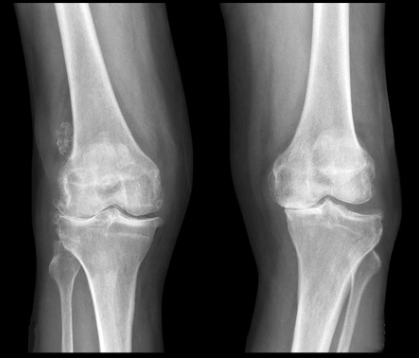

膝の痛みの場所や圧痛の有無、可動域や水が溜まっているかなどをチェックします。またレントゲンで膝の関節の隙間が減っていないか、変形がないかを確認します。

年齢を重ねるにつれて膝の軟骨の弾性が低下し、徐々に軟骨がすり減り膝の痛みの原因となることがあります。これを変形性関節症と言います。更年期を過ぎた女性に多く、体重がかかる膝の内側が痛むことが多いです。変形が進むと、内側の隙間がすり減り、O脚となることが多いです。初期は立ち上がりの膝の痛みが中心で、安静にすると痛みは改善します。しかし、進行すると階段や正座でも痛み、最終的に体重をかけていない時も痛みが出るようになります。